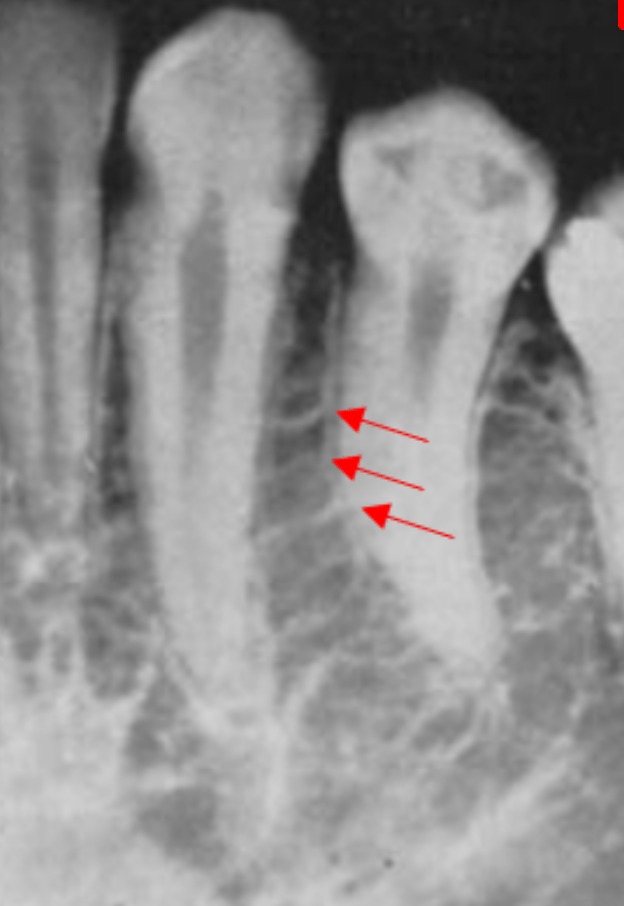

The arrows are point to this structure

Nasal Fossae